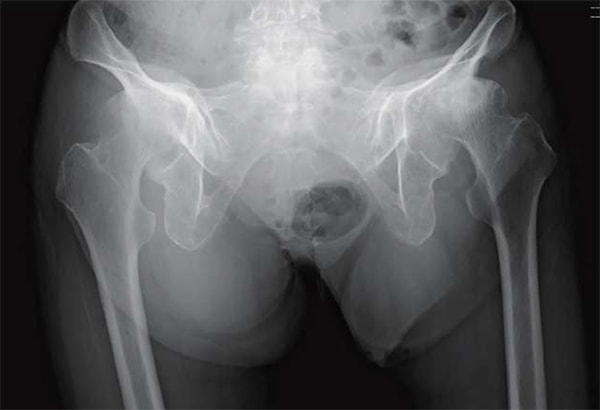

変形性顎関節症

変形性膝関節症に対する手術件数は東京都で2番目に多い実績を誇り(手術数でわかるいい病院/週刊朝日MOOKより)、骨切り術、人工膝関節単顆置換術、人工膝関節全置換術とすべての術式による加療が可能な点が特徴です。どの術式が患者様の生活様式に最良か、患者様と相談、検討を重ねながら決定させて頂いております。

日常の移動手段として自転車乗車が欠かせない方、ゴルフや卓球、スキーといったスポーツ活動も継続したい方など、高齢化社会において患者様の背景、ニーズは多様化しております。人工膝関節置換術は除痛のみならず、中間屈曲位の安定性、深屈曲が求められる時代となりました。当科ではスポーツ復帰率を高めることを目標に、術式、術後疼痛コントロールの改良を重ねるなかで、より満足度の高い手術成績が得られるようになったと思います。

また、保存治療においても外来での投薬、生活指導のみならず、多血小板血漿(PRP)や歯髄幹細胞培養上清の関節内投与といった再生医療も提供させて頂いております。人生100年時代を謳歌できるよう、歩行から患者様を支えさせて頂く。そのような施設であり続けたいと考えておりますので、+αの御加療が必要な患者様がいらっしゃいましたらご相談ください。

人工股関節置換術において従来の後側方アプローチ(Posteo Lateral Approach)に加えて、2015年より前方アプローチ(Direct Anterior Approach)を積極的に取り入れて参りました。

これは脱臼率の低下に加えて、筋間アプローチによる低侵襲手術を提供するという目的によるものです。これにより在院日数は低下し、術後の姿位制限を撤廃したことで、前述のスポーツ復帰率の向上を図ることができるようになりました。また、高齢化に伴い生じる脊椎変形、脊椎固定術後の矢状断アライメントの変化に対応できるよう、CUPは透視を用いて動的に評価しながら至適位置に設置することで良好なstabilityが得られています。

当科は膝、股関節手術ともに周術期の合併症が非常に少ないのが特徴ではありますが、全身状態に変化があった際は即対応できるのが、総合病院である当院の強みであると思います。各科と連携をしながら患者様が安心できる入院期間を過ごしていただいております。